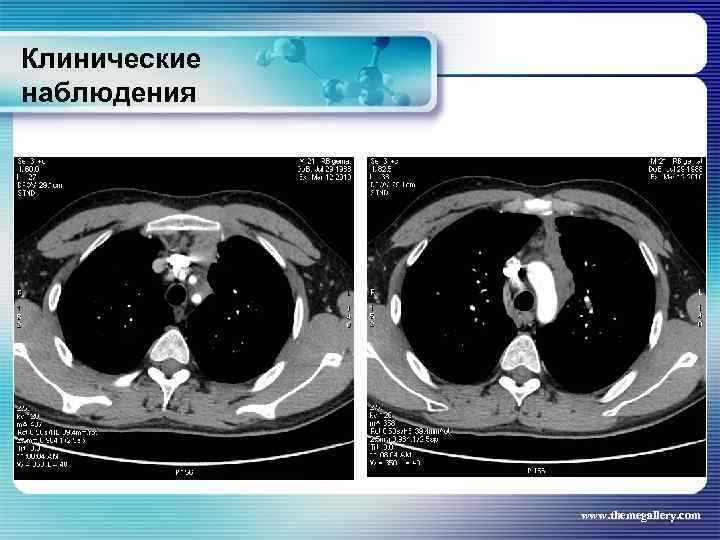

Клинические наблюдения Тот же пациент На основании выполненных исследований сформулирован клинический диагноз: лимфома Ходжкина, нодулярный склероз Grade II, III A E S стадия с поражением шейных, заднешейных, надключичных лимфатических узлов, средостения с прорастанием в левое легкое и плевру слева, внутригрудных лимфатических узлов, абдоминальных лимфатических узлов, селезенки. За время наблюдения проведено 8 циклов BEACOPP. На этом фоне достигнута в марте 2010 года парциальная ремиссия. При лучевом обследовании выявлена положительная динамика изменений. www. themegallery. com

Клинические наблюдения Тот же пациент На основании выполненных исследований сформулирован клинический диагноз: лимфома Ходжкина, нодулярный склероз Grade II, III A E S стадия с поражением шейных, заднешейных, надключичных лимфатических узлов, средостения с прорастанием в левое легкое и плевру слева, внутригрудных лимфатических узлов, абдоминальных лимфатических узлов, селезенки. За время наблюдения проведено 8 циклов BEACOPP. На этом фоне достигнута в марте 2010 года парциальная ремиссия. При лучевом обследовании выявлена положительная динамика изменений. www. themegallery. com